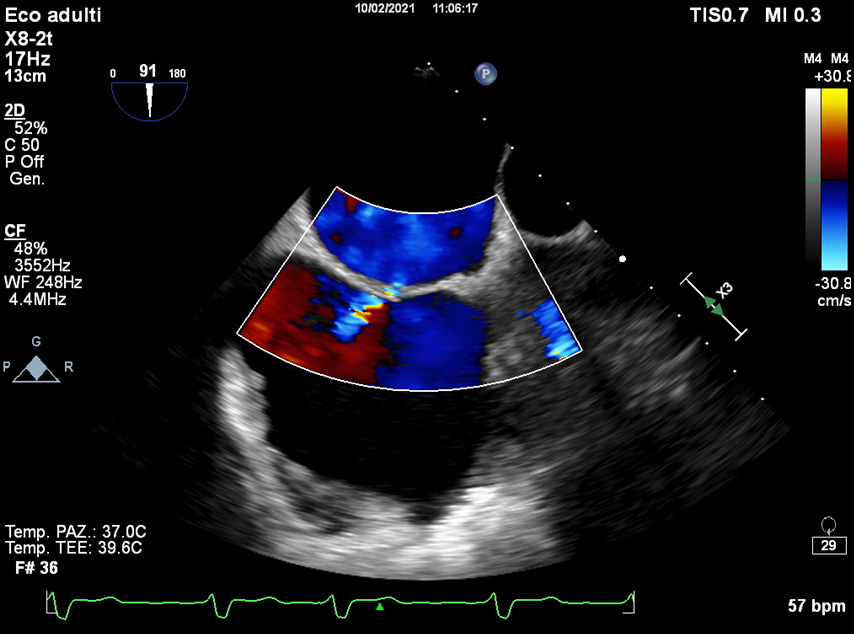

The main TOE e/o CCTA exclusion criterion is the existence of thrombus in the LAA [35]. Nowadays, TOE is the most used imaging technique to exclude the presence of thrombi in LAA (Fig. 3).

Fig. 3.The main TOE e/o CCTA exclusion criterion is the existence of thrombus in the LAA (see arrow).